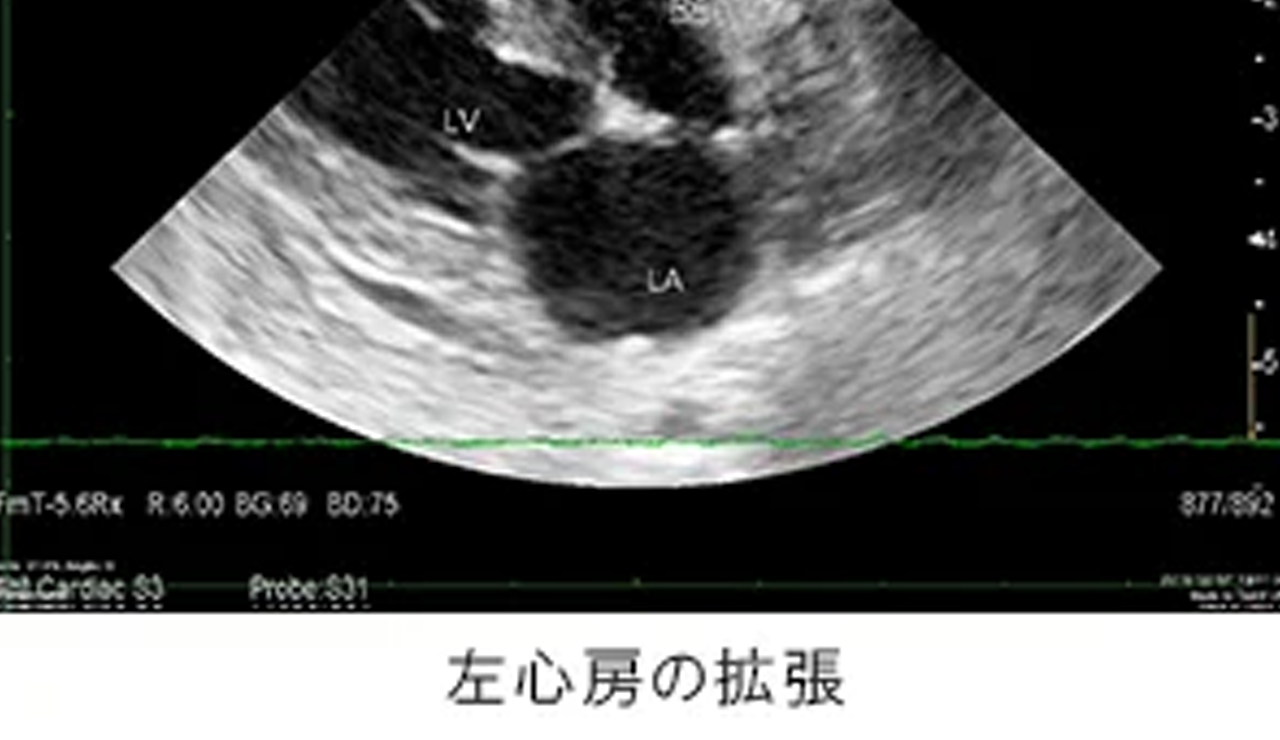

初期には症状が出ないことも多く、精密検査ではじめて発見に至ることも多い動物の心臓病。年齢とともに罹患率も高まり、重篤化しやすいため、定期的な診察を通じて早期発見・早期治療を心がけましょう。

ピジョン動物愛護病院では、各院いずれもレントゲン検査や最新の超音波検査装置による心臓の精密検査を実施しています。

| 動物の小さな心臓の動きが詳細に評価可能な検査装置。 心臓内における血液の速度や方向、弁膜の構造を痛みを伴うことなく評価でき、正確な診断と治療を可能にします。 |